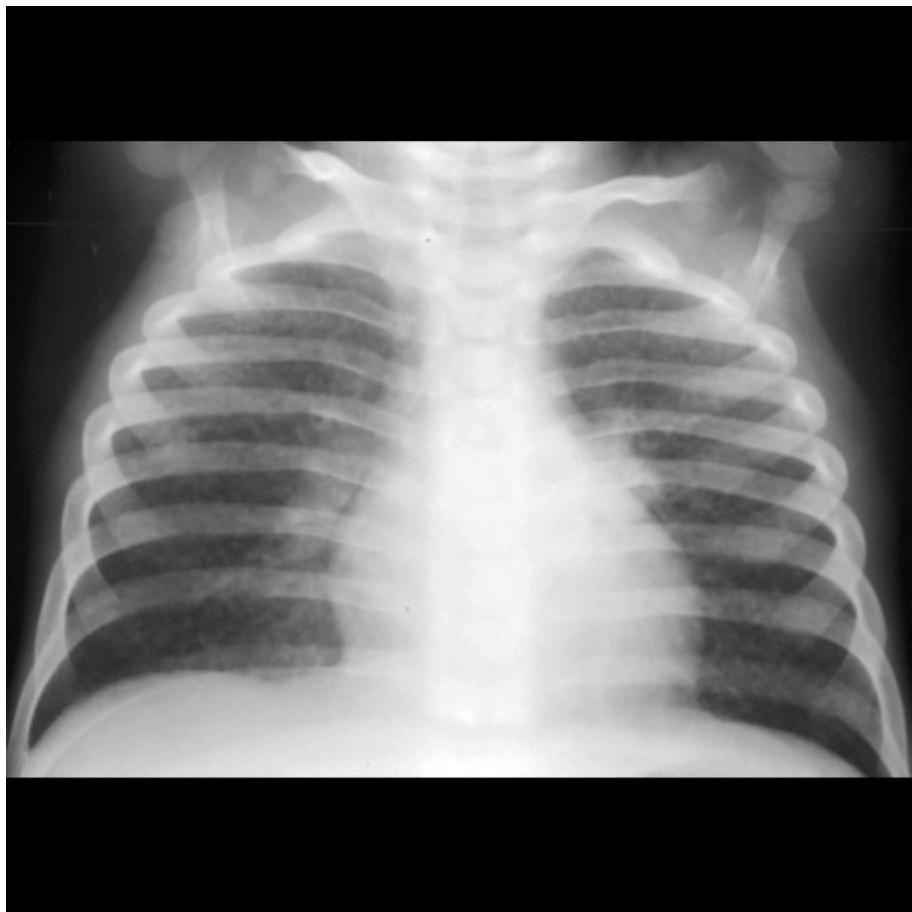

- Manifestations: Positive TST or IGRA with mild chest radiograph abnormalities (atelectasis, infiltrate, hilar adenopathy, Ghon complex).

Pediatric chest x-ray showing hilar lymphadenopathy tuberculosis.

- Hilar/Mediastinal Adenopathy: Most common abnormal finding; often the only visible abnormality in early disease.

Radiography is cornerstone for diagnosis in children due to clinically silent presentations. All lobar segments equally at risk for initial infection. • 25% of cases involve two or more lobes • Hilar lymphadenopathy inevitably present • Partial bronchial obstruction causes air trapping • Progressive destruction leads to cavitation

Diagnostic Imaging Findings Normal Chest X-ray Children with latent TB infection (LTBI) usually have normal-appearing chest radiographs. An isolated calcified lesion with positive TST can be treated as LTBI. Hilar/Mediastinal Adenopathy The most common abnormal radiographic finding in pediatric pulmonary TB. May be the only visible abnormality in early disease. Other Findings Infiltrates, atelectasis, pleural effusions, cavity lesions, or miliary disease pattern may be present in advanced cases.